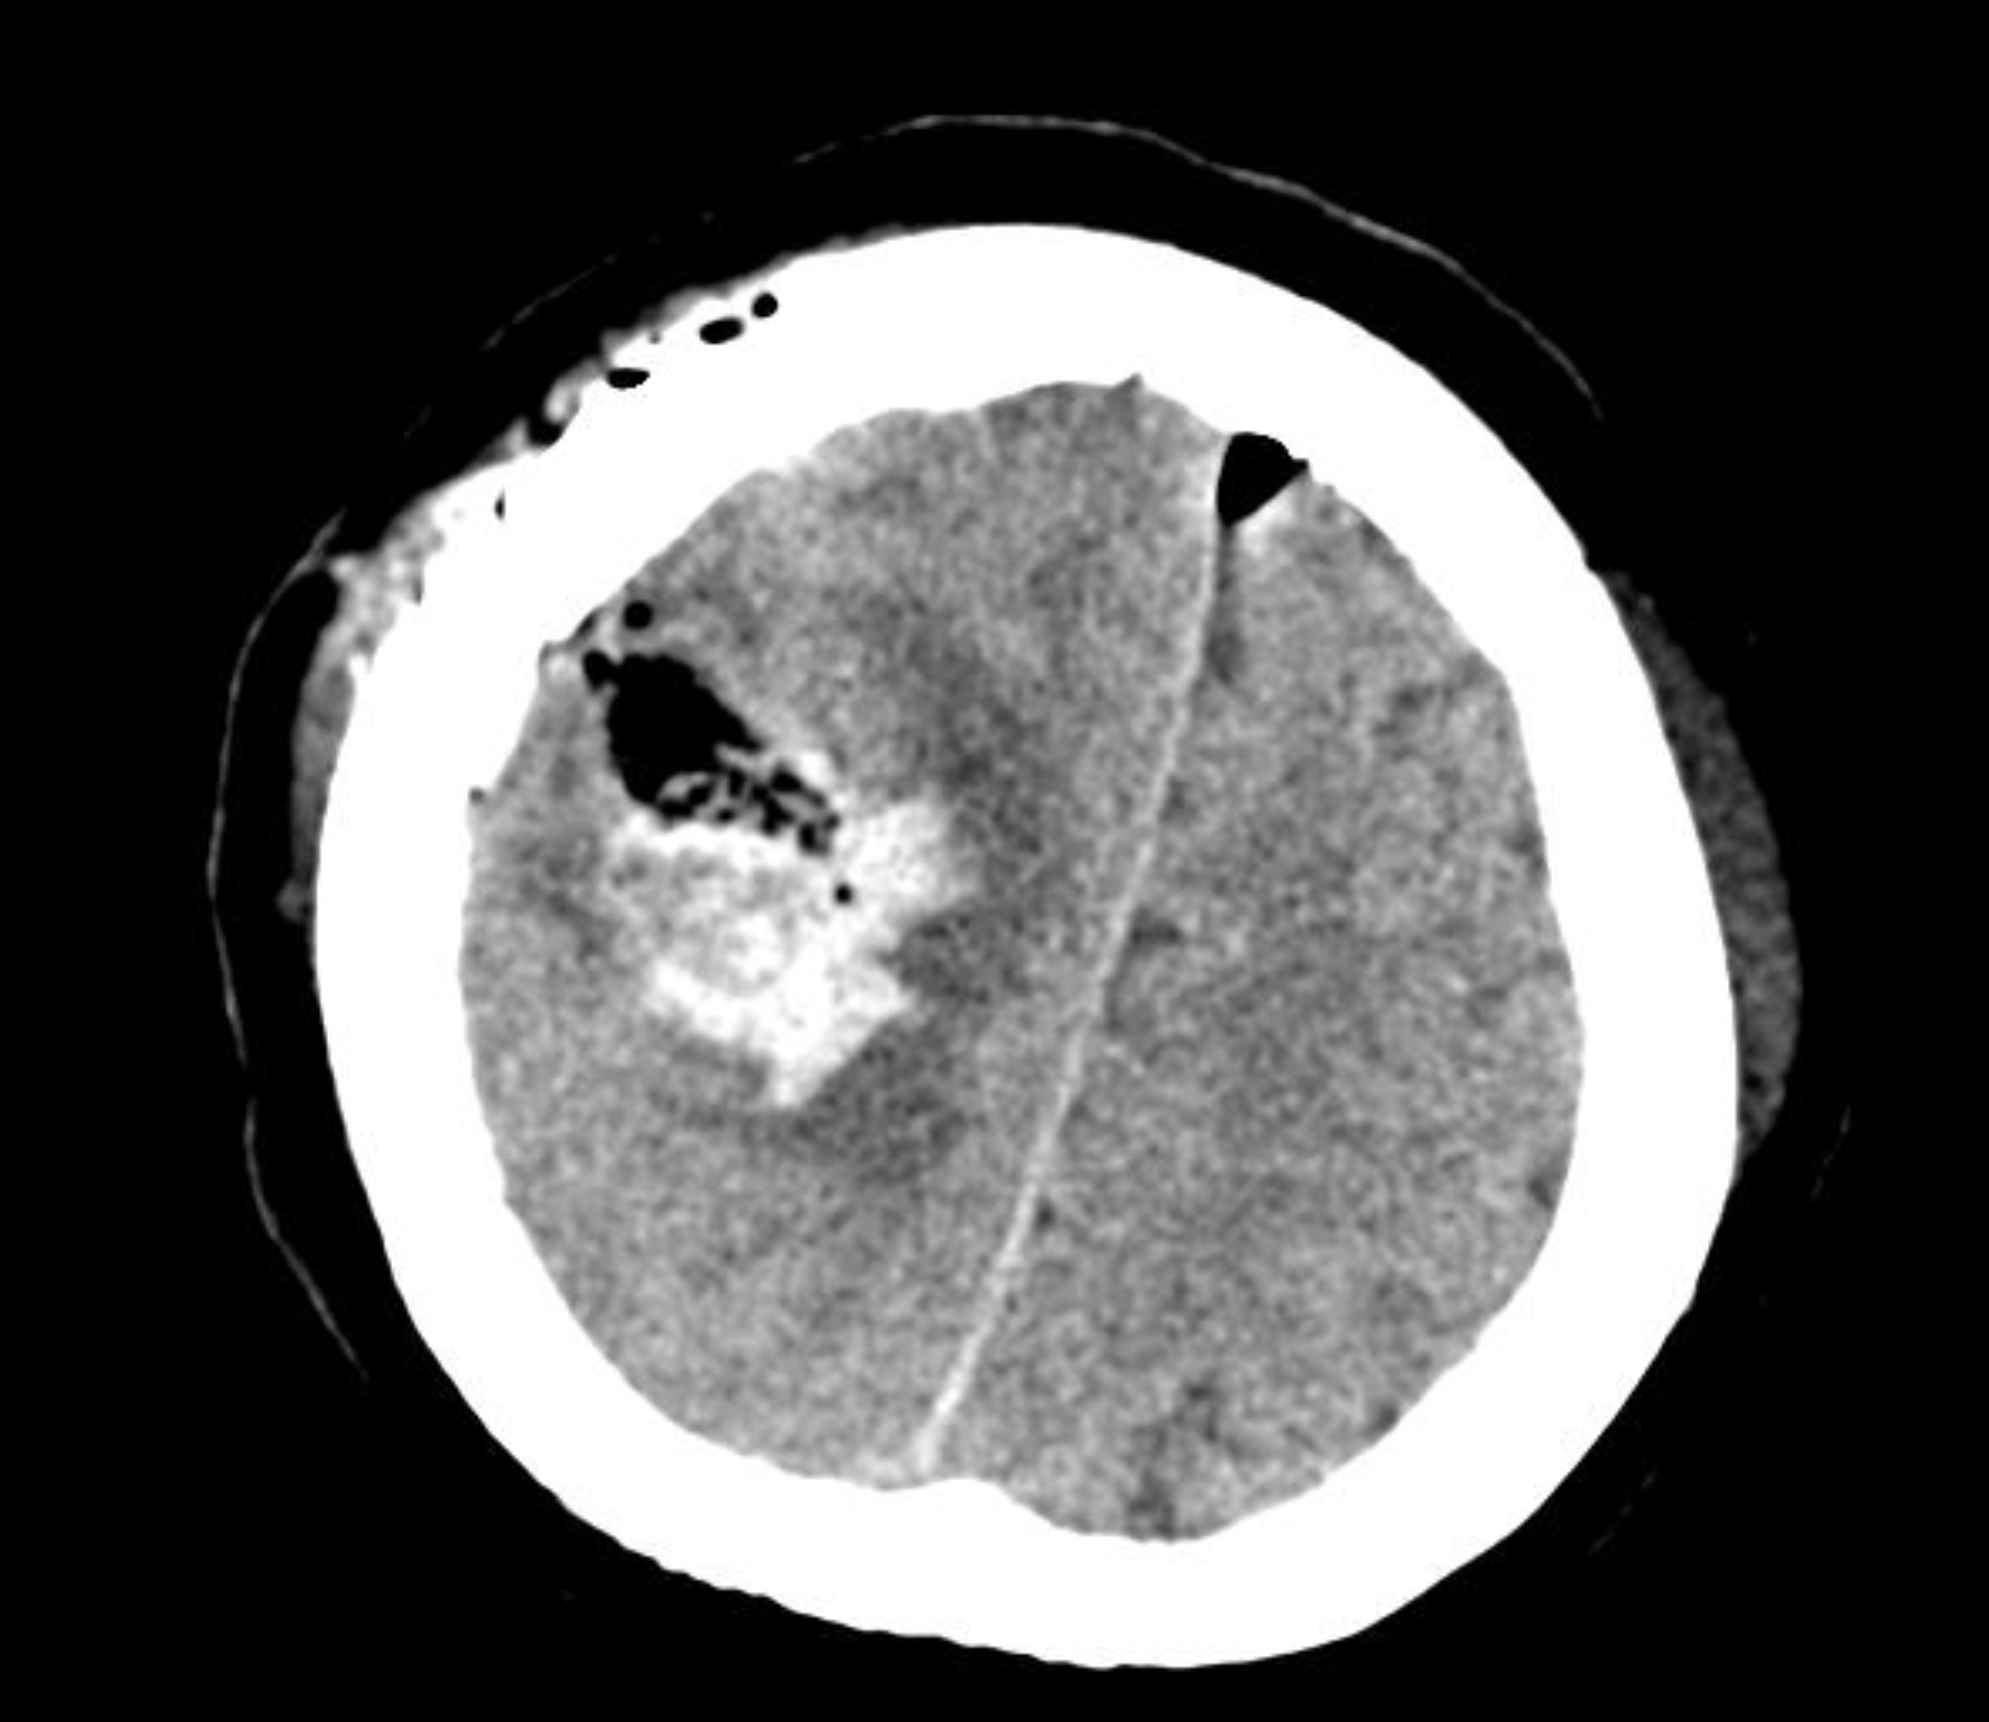

Our case was a 49-year-old woman with a history of a right parotid painless mass lesion, which had grown 5-6 cm over eight months. Fine needle aspiration cytologic evaluation of parotid lesion was consistent with monomorphic adenoma, based on available cytologic reports from another center. The patient underwent a right parotidectomy at the same center. Histological examination indicated ACC with dedifferentiated components. Some adverse histologic factors, including more than two mitoses/10 HPFs, perineural/vascular invasion, tumor necrosis, and extracapsular invasion, were also identified on microscopic examination (Figure 1, A and B). The patient underwent t 30 sessions of radiotherapy. After two months, she experienced sudden severe left hemifacial paresis. Brain CT scan imaging demonstrated a 45*40 mm heterogeneous itrapa-renchymal cerebral hemorrhage in the right frontoparietal lobe with surrounding edema, which caused a 6 mm midline shift to the left side (Figure 2). She became a candidate for craniotomy at our center with the clinical impression of intracranial hemorrhage. Tissue samples were sent to the pathology department. Gross examination of the specimen showed multiple fragments of tanish gray soft fragile tissue. Microscopic study of the brain tissue showed a neoplasm composed of a mixture of different cell types, including most large polygonal cells with round to small oval nuclei, stippled chromatin pattern, and abundant basophilic granular cytoplasm. Some vacuolated cells and some cuboidal cells with eosinophilic cytoplasms and small dark nuclei were arranged in solid, follicular, and microcystic patterns (Figure 3 A and B). The cytoplasmic granules demonstrated diastase-resistant periodic acid-Schiff (PAS-D) positivity (Figure 4). Some foci were also observed with histologic features of the undifferentiated carcinoma, composed of atypical cells with pleomorphic nuclei, prominent nucleoli, and abundant mitotic figures (Figure 5). In the immunohistochemical study, tumor cells were positive for cytokeratin and showed DOG 1 positivity with apical membrane staining (Figure 6). Therefore, metastatic ACC with dedifferentiated components was diagnosed.

Fig. 2.Brain CT scan. A heterogeneous intraparenchymal cerebral hemorrhage in the right frontoparietal lobe with surrounding edema